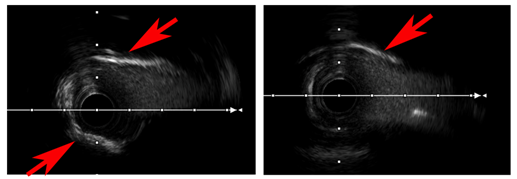

左图是旋磨之前的血管里面的样子,红色箭头所指就是我们所说的“钙化圈”,整个包绕住血管,使得血管里面血液流动十分有限。

右图则是旋磨后,可以看到钙化的东西被磨掉许多,只留下薄薄的一点,此时我们再用工具去扩大血管腔,就容易的多。